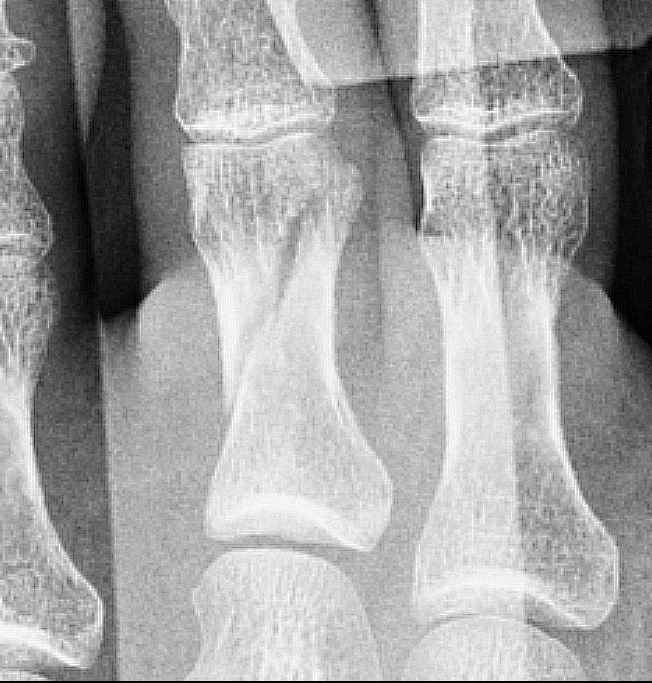

ดามเฝือกนิ้วเท้าครบ 5 สัปดาห์ หลังถอดที่ดามออก นิ้วเท้าตึงงอนิ้วลำบาก เป็นปกติหรือเปล่าครับ

ดูในเอกซเรย์ กระดูกเริ่มติด หมอให้เอาที่ดามออกได้

รู้สึกนิ้วเท้ามันตึงๆ แข็งๆ งอนิ้วลำบาก

ที่มันเป็นเพราะมันอยู่ในช่วงกำลังสร้างกระดูกหรือเปล่าครับ

แล้วแบบนี้ถือว่า เป็นปกติ หรือเปล่าครับ

อันนี้ภาพกระดูกนิ้วเท้าที่หักตอนช่วงแรกๆ ครับ